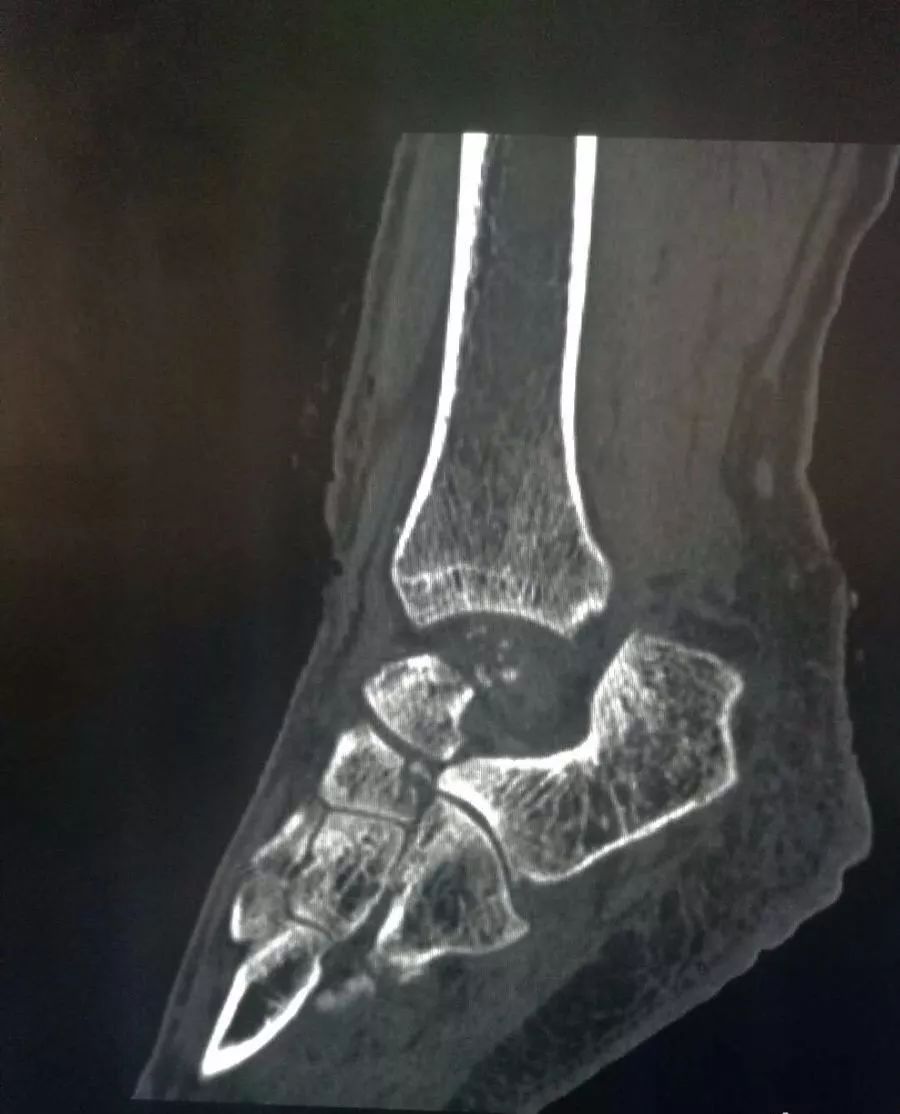

图片中心是骨缺损区

一位43岁的女患者因不幸遭遇车祸,造成距骨粉碎骨折、脱出,导致左踝关节开放性脱位并距骨体缺损,踝关节活动受限,属罕见的病例。据骨科专家贺西京教授介绍,距骨是人体踝关节的一个关键部分,主要支持脚向各个不同的方向上移动,是连接下肢和足部的枢纽,肩负重力传递和运动的耦联,是足部重要的功能单位。距骨缺失造踝关节功能丧失造成患者的踝关节屈伸功能不变。面对距骨的缺失,传统的治疗方法是进行踝关节融合术,会造成踝关节活动丧失,人工距骨置换可以实现踝关节和距下关节的运动,这就使足部可以上下左右的运动,使病人重新获得活动的能力。

2017年12月29日,西安高新医院特聘骨科首席专家、3D打印医疗器械专业委员会专家委员贺西京教授和其团队成功为这位43岁的女性患者施行了3D打印个性化定制人工距骨假体植入手术,经有关文献检索个性化3D打印人工距骨植入术是西北地区首例,目前全球仅完成4例这类手术,这一具有领先水平的数字化、精准化、个性化的临床应用技术,达到国内外先进水平。